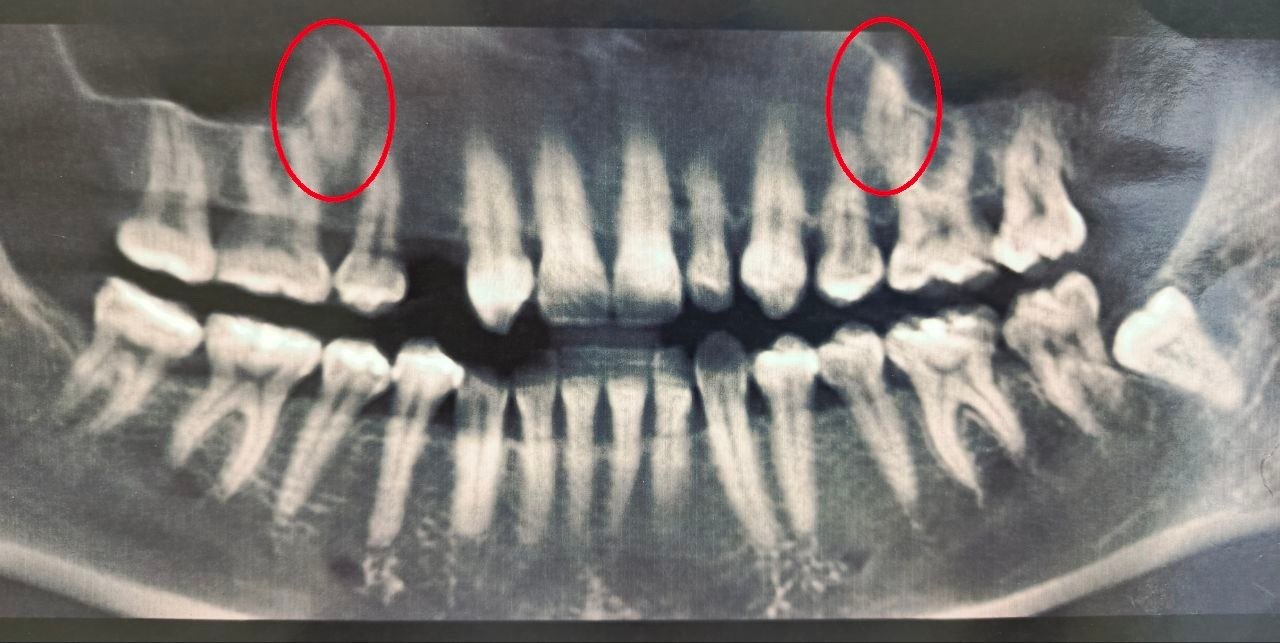

Необычный случай начался в 2023 году, когда пациентка обратилась к специалистам. В челюсти находились два непрорезавшихся зуба.

Врачи приняли решение «вытянуть» непрорезавшиеся зубы.

На сегодняшний день один зуб уже полностью вышел из костной ткани и занял свое законное место. Второй успешно проходит последний барьер - кортикальную пластинку челюсти - и вскоре тоже встанет в ряд.